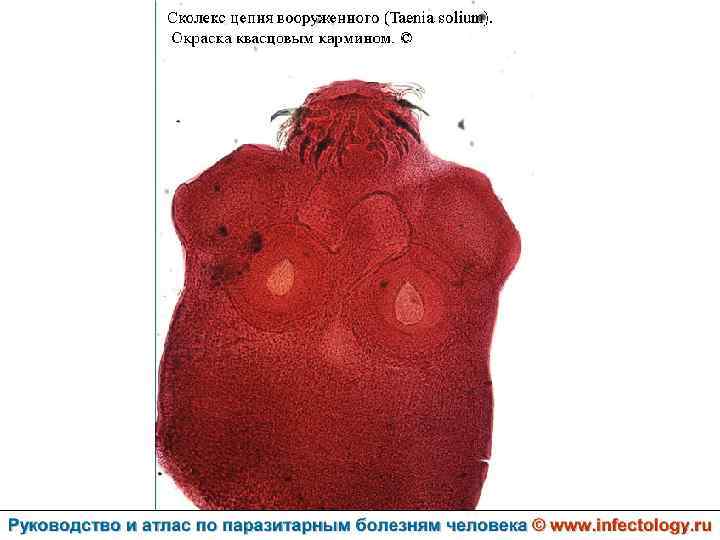

Тениоз (шифр по МКБ 10 - B 68. 0) – антропонозный биогельминтоз, одним из основных клинических проявлений которого является нарушение функций желудочно– кишечного тракта.

Цистицеркоз (шифр по МКБ 10 - B 69) – биогельминтоз, который вызывается паразитированием в тканях и органах человека и животных личиночной стадии цепня вооруженного – цистицерка (Cysticercus cellulosae) Болезнь проявляется разнообразными симптомами в зависимости от локализации цистицерков.